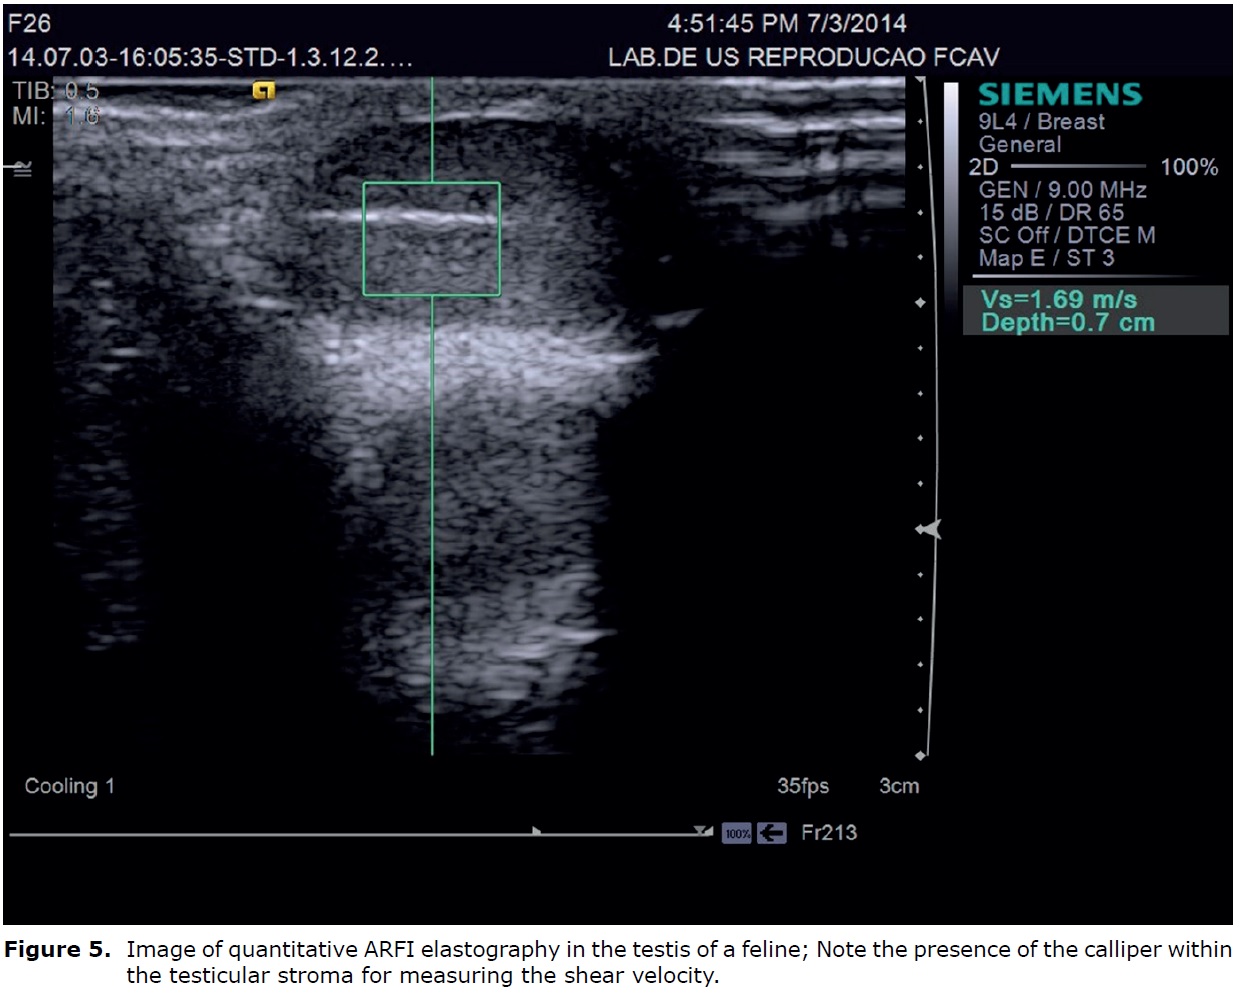

In qualitative ARFI, short acoustic pulses and high intensities are used to deform the elements of the tissue and create a static map (elastogram) of the relative stiffness of the tissue. Alternatively, the quantitative approach to ARFI utilizes a primary acoustic impulse sent towards a region of interest and promoting the formation of pressure waves capable of deforming the tissues to raise the speed of the wave propagation (shear velocity). The wave velocity and the attenuation of acoustic pressure waves are both related to the rigidity and viscoelasticity of the tissue; the waves have a greater velocity in rigid tissues (40).

This technique was used to evaluate the testes of healthy cats providing novel information on testes elastographic parameters in clinically healthy cats, such as the quantitative values for tissue echogenicity, qualitative and quantitative findings of ARFI elastography. The testes examined by qualitative elastography were free of any malformations and the images appeared as homogeneous dark areas (Figure 4). The mean shear velocity values reported were 1.51 m/s (95% confidence interval: 1.42 and 1.59 m/s) for the right testicle and 1.48 m/s (95% confidence interval: 1.41 and 1.54 m/s) for the left testicle of the felines. There was no significant difference when comparing the right and left testicular structures (44) (Figure 5).

Quantitative and qualitative ARFI elastography of the testes in cats is easily performed. Furthermore, the reference values for testicular elastography in healthy cats, the differences in shear velocity values of diseased tissues can be evaluated to differentiate between benign and malignant tumours in felines, once the definitive diagnosis of benign or malignant lesions is made only by histopathology after castration, considered a invasive method, which promotes the loss of the reproductive value of animals (44).